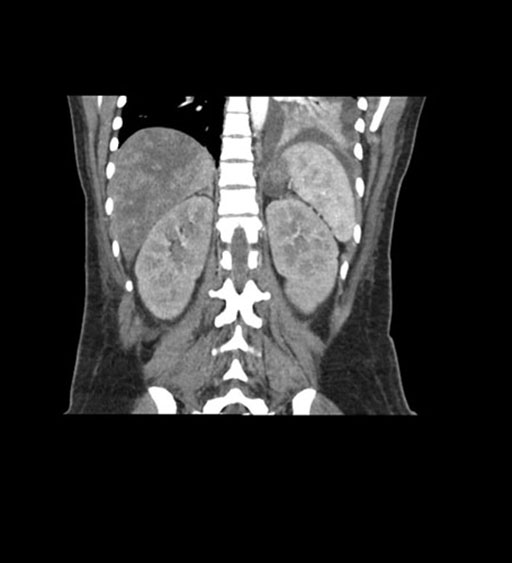

Coronal Arterial